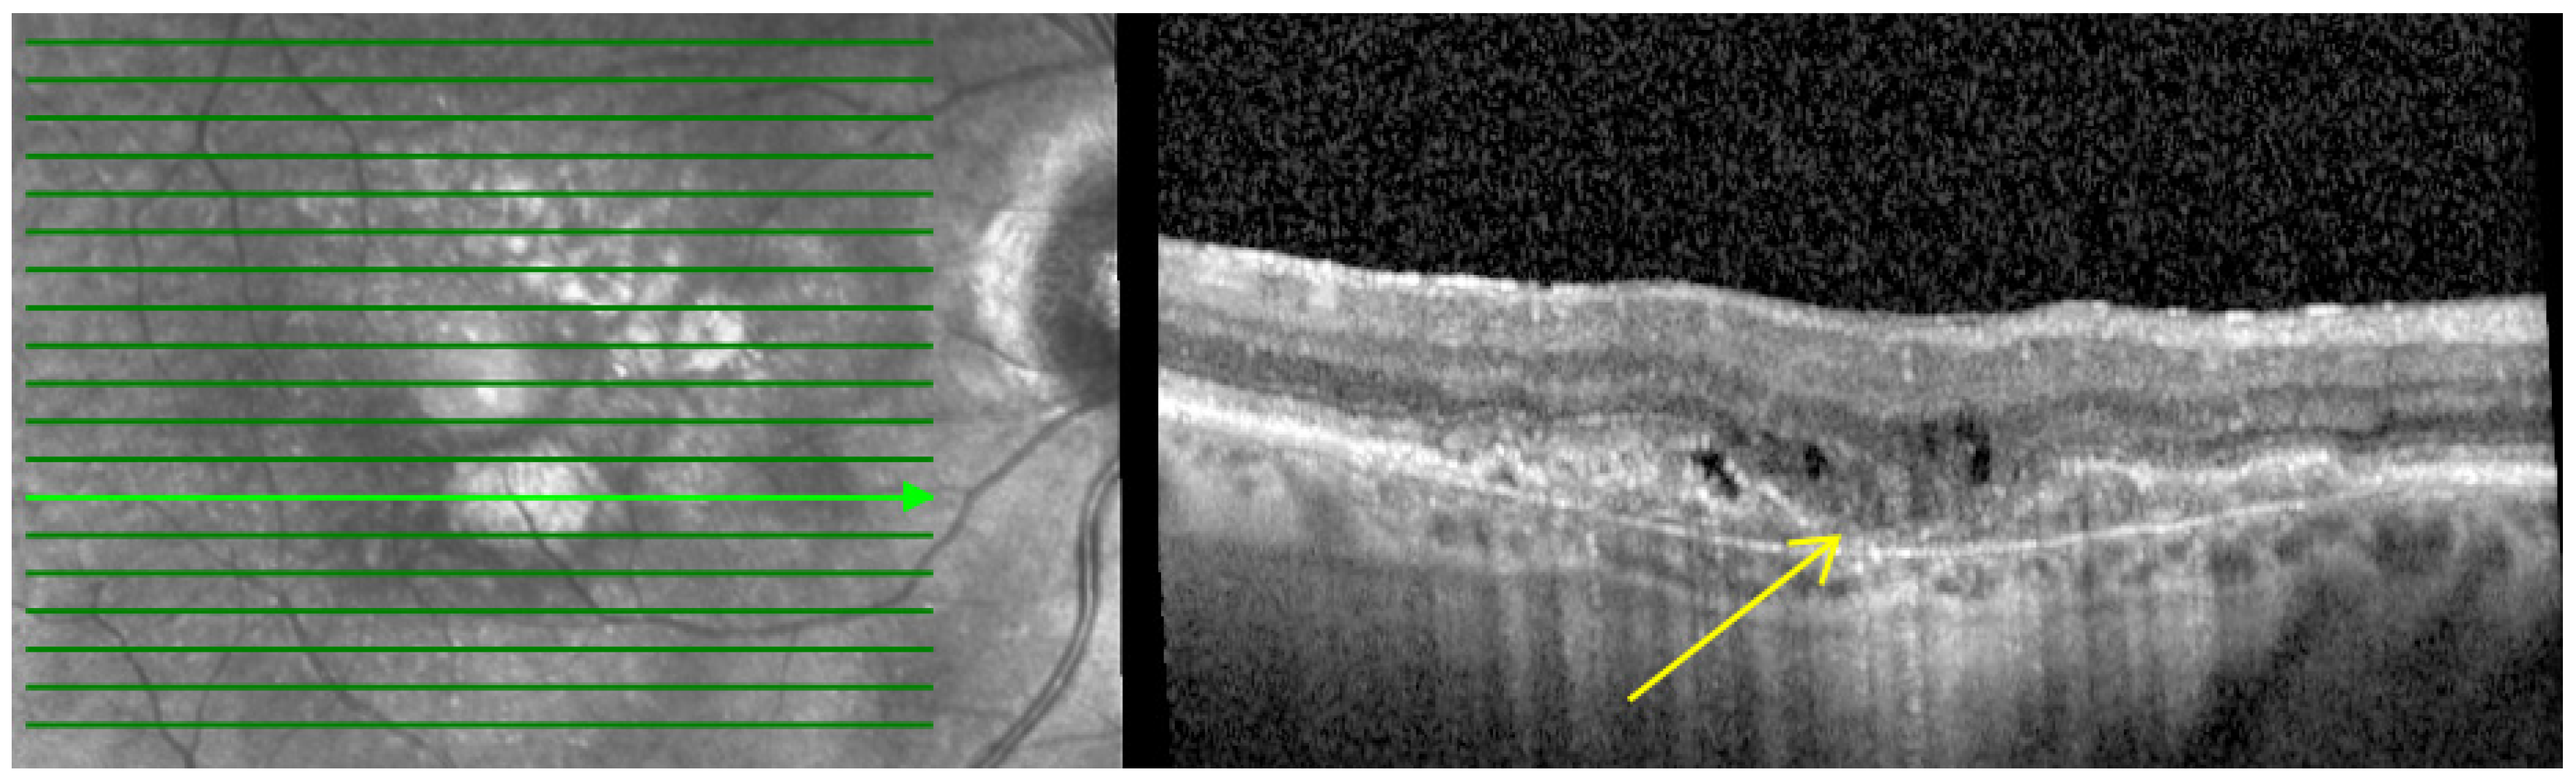

- Macular atrophy (MA): Characterized by in-lesion photoreceptor death and visual impairment and typically follows progressive atrophy and thinning of the retinal pigment epithelium (RPE) and choriocapillaris. The loss of photoreceptors can be detected by the thinning of the Henle fiber layer. This could be detected by OCT by features such as loss of the ellipsoid layer and outer limiting membrane as well as thinning of the outer nuclear layer, which together with the Henle fiber layer and photoreceptors appear as a single hyporeflective band on OCT images as shown in Figure 1 [24,25,26].